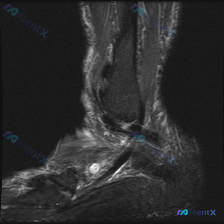

这是踝关节矢状位T2加权压脂序列MRI,核心问题是图像中可见软组织液信号,我们来拆解分析:

- 核心异常定位:距骨下方、跟骨上方的跗骨窦区域,存在明显信号异常

- 跗骨窦内可见一个圆形/椭圆形边界清晰的高信号灶,整个跗骨窦正常低信号韧带结构模糊消失,代之以弥漫性高信号,提示该区域存在软组织水肿、炎症渗出或滑膜增生

- 距骨、跟骨骨皮质完整,无明确骨折线,但距下关节间隙内可见积液高信号,提示距下关节存在滑膜炎/积液

- 踝关节周围皮下软组织也可见弥漫性水肿高信号